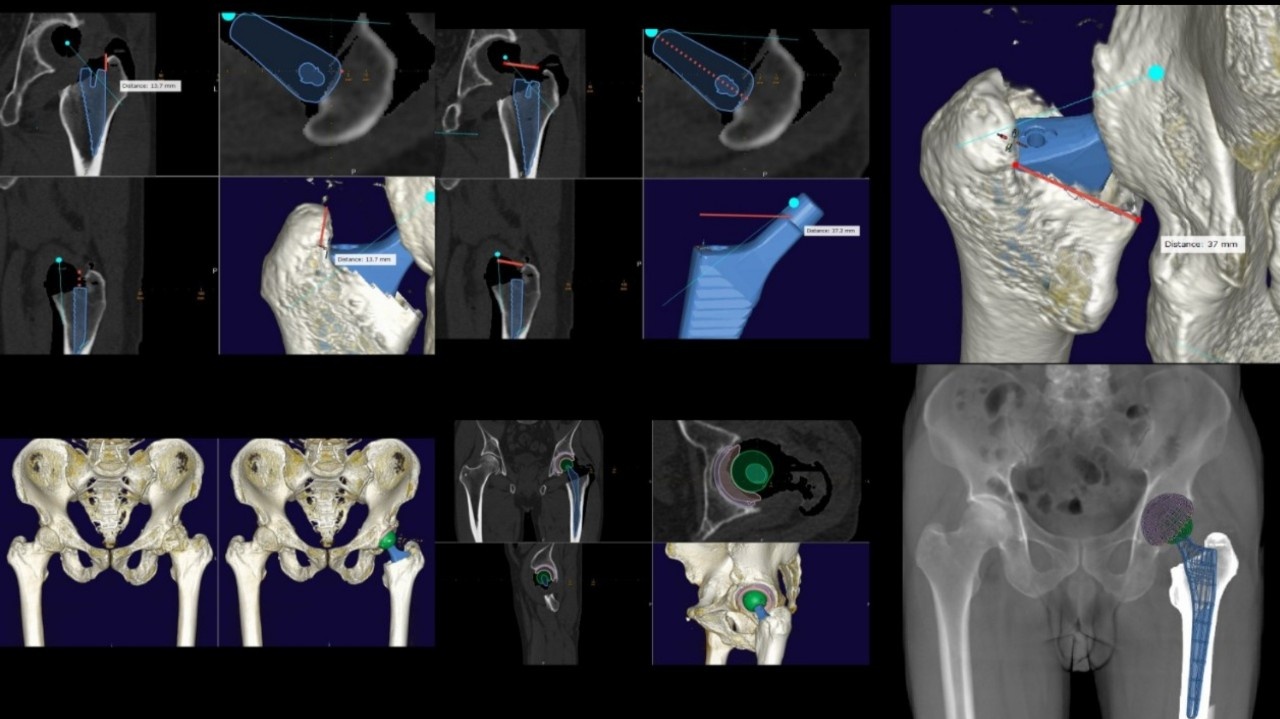

Hình ảnh kế hoạch phẫu thuật khớp háng được mô phỏng trên máy tính trước mổ.

Sau khi lựa chọn loại khớp nhân tạo được "cá thể hóa", các bác sĩ sẽ sử dụng những phần mềm chuyên dụng để lập kế hoạch chi tiết cuộc mổ. Quá trình này giúp xác định chính xác vị trí cần đặt các cấu phần khớp nhân tạo, tối ưu hóa biên độ vận động của khớp sau mổ, tránh rủi ro cứng khớp hay đi lại tập tễnh.

Bên cạnh đó, quá trình còn giúp tiên lượng một số rủi ro xuyên suốt quá trình phẫu thuật. Thậm chí, bệnh nhân và người nhà còn có thể tham gia cùng bác sĩ để hiểu một cách trực quan nhất những gì có thể xảy ra với cuộc phẫu thuật.